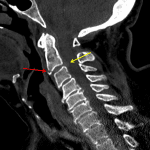

- Small minimally displaced corner (“teardrop”) fracture involving the anteroinferior endplate of C2

- Nondisplaced fracture through the anterior tubercle of the left C2 transverse process extending into the transverse foramen

- Prominent central disc herniation at C2-C3 which effaces the ventral CSF and contacts and mildly deforms the ventral cord

- Teardrop fracture

Acute minimally displaced corner (“teardrop”) fracture involving the anteroinferior endplate of C2. Consider MRI to further assess for ligamentous injury.

Acute nondisplaced fracture through the anterior tubercle of the left C2 transverse process extending into the transverse foramen. Recommend neck CTA to assess for vascular injury.

Prominent central disc herniation at C2-C3 which effaces the ventral CSF and contacts and mildly deforms the ventral cord. Though age-indeterminate, this could represent an acute traumatic disc herniation, which could be further assessed with noncontrast C spine MRI.